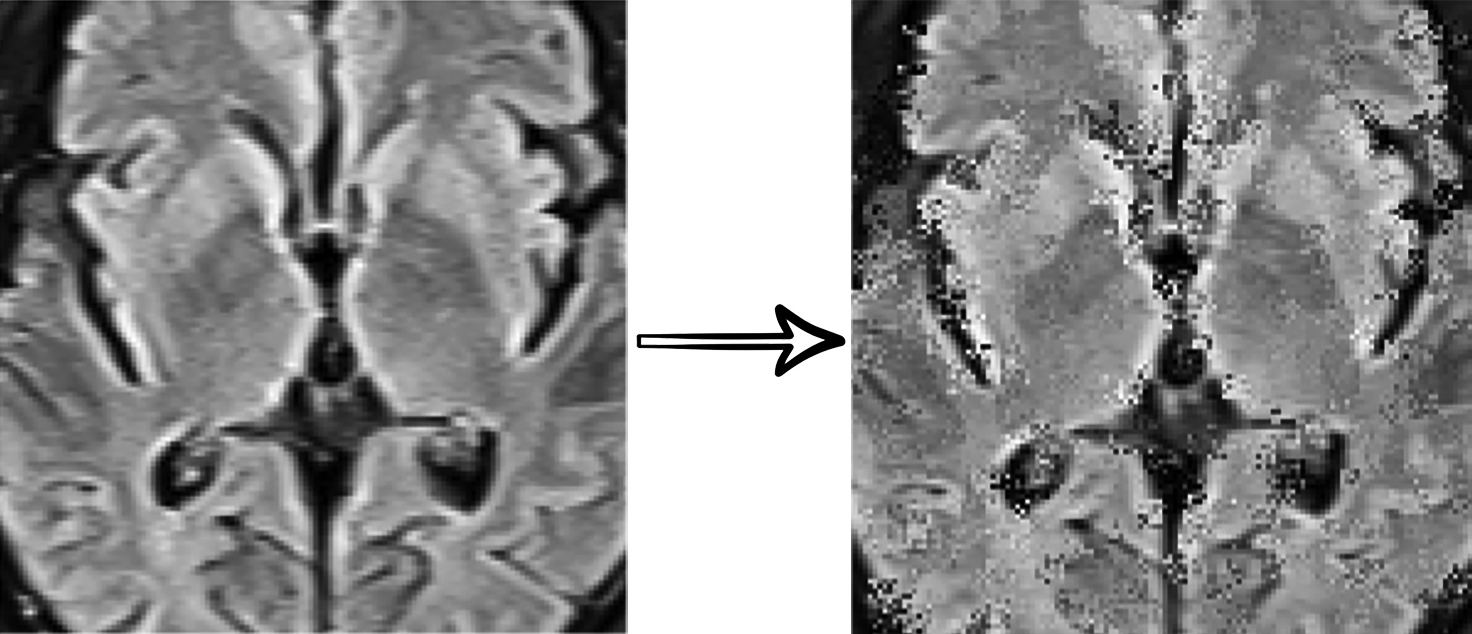

In this work, we use a self-supervised learning method to extract specific features of our data from multiple perspectives (appearance, texture, context, etc.) by combining three different supervision tasks that were proposed in “Models Genesis” [31]. Our model consists of a U-Net [25] with a ResNet [9] encoder. Each supervision task consists of a particular transformation and reconstructing the original image from the transformed one (see Fig. 3). Finally, the encoder part of the network is fine-tuned for the target classification task.

Refer to caption

(a) Non-linear transformation

(b) Local shuffling

(c) In-painting

(d) Out-painting

Figure 3: Self-supervised transformations: (a) Non-linear Intensity Transformation enforces the model to learn the shape and intensity distribution as the appearance of organs.(b) Local Pixel Shuffling enforces the model to learn local boundaries as the texture of organs. (c,d) Out-painting and In-painting enforces the model to learn geometry and spatial layout of organs via extrapolating and local continuities of organs via interpolating as the context of images, respectively.